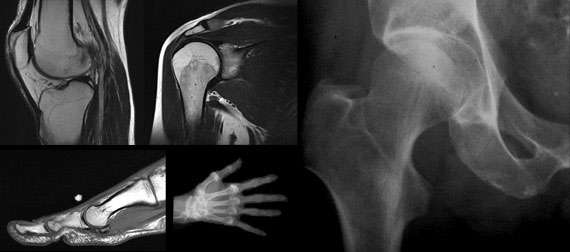

Musculoskeletal Radiology performs the full range of musculoskeletal imaging using a variety of modalities, including general radiography, CT, MRI, and arthrography. Radiologists in this subspecialty also assist in the interpretation of musculoskeletal radionuclide bone scans, read in conjunction with a nuclear medicine physician.